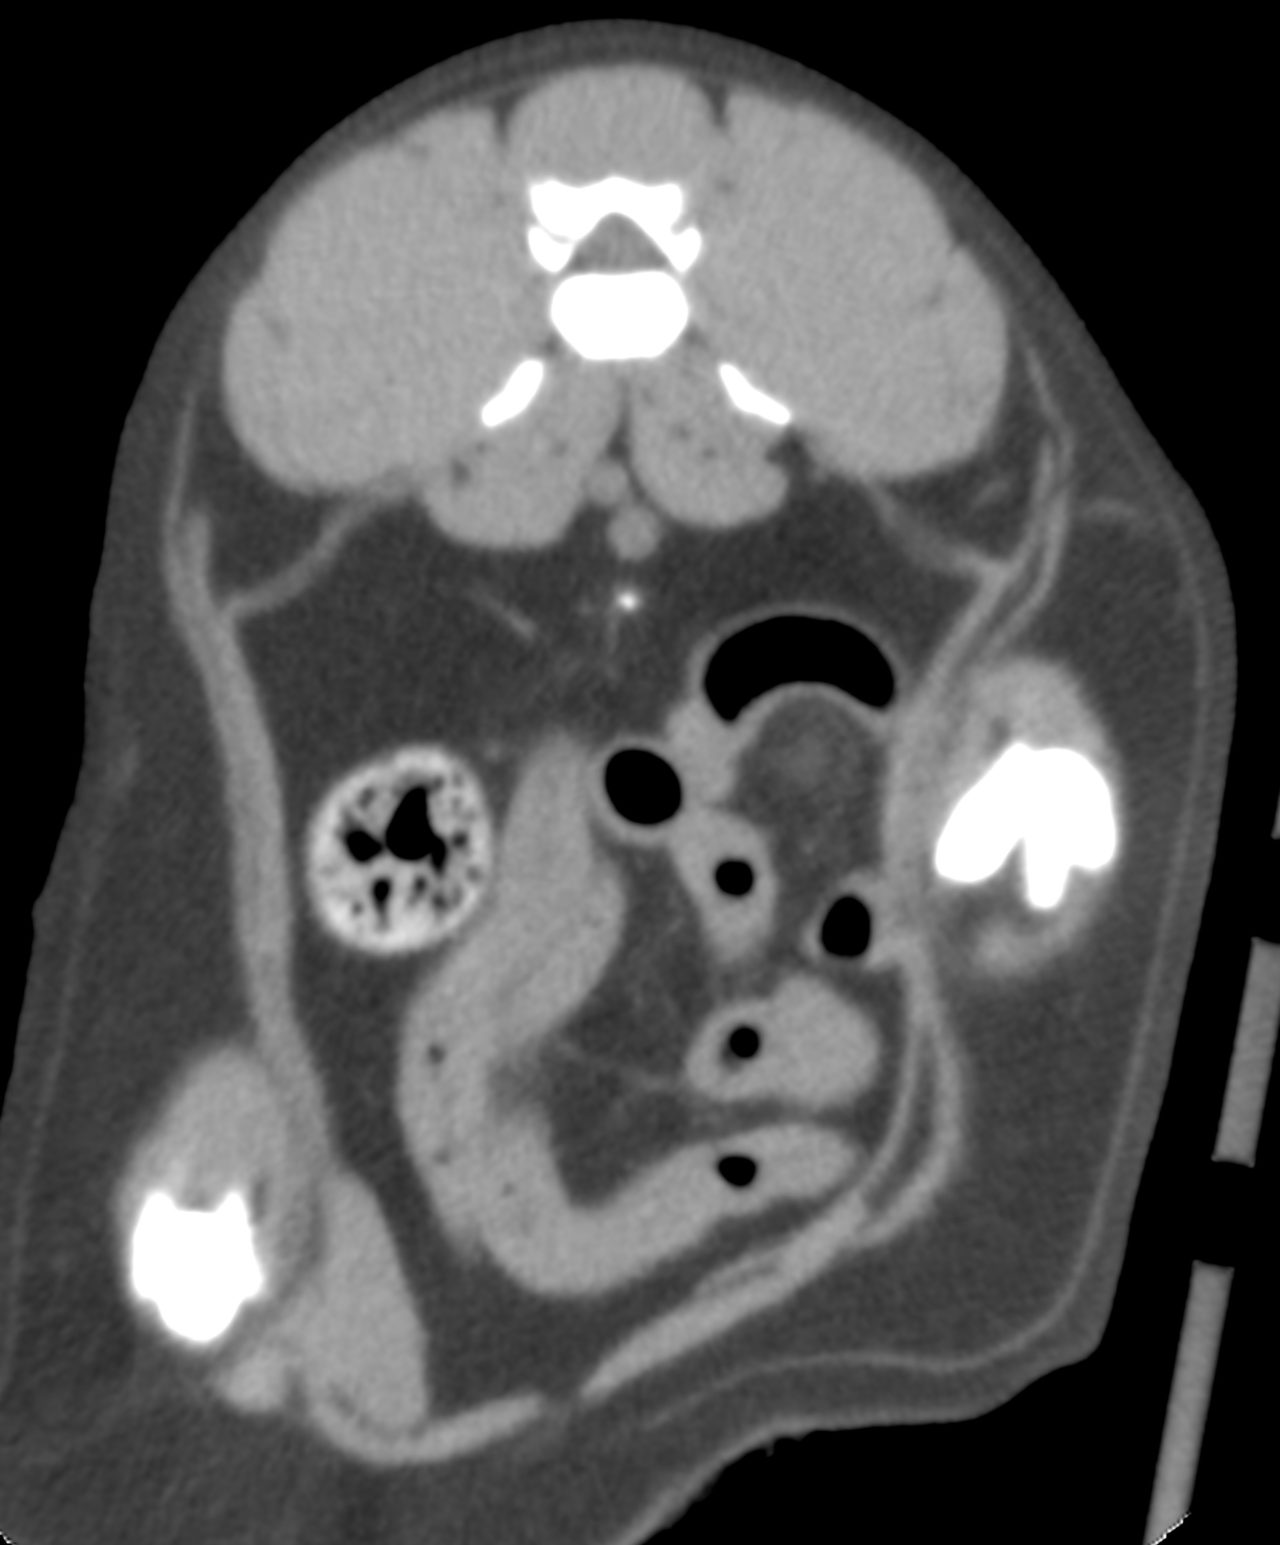

たった1mmの大きさの尿管結石でも猫の尿管を閉塞してしまうことがあります。血液検査、尿検査、超音波検査、無麻酔CT検査などで外科的に対応すべきか?詳しく評価します。閉塞してもすぐには腎盂の拡張はそれほど顕著ではありませんし、片側のみであれば血液検査に異常値が検出されないこともしばしばです。マイクロサージェリーで短尺ステントと尿管新吻合術で対応しました。通常はシュウ酸カルシウムであり溶解できないので非常に厄介です。